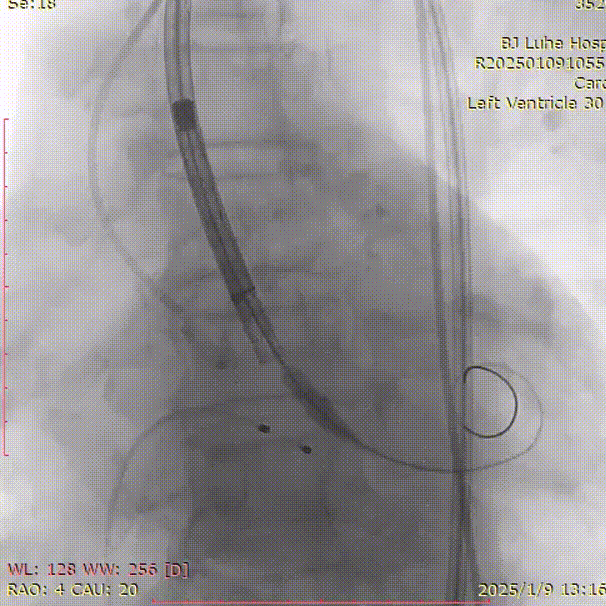

术中影像

术前下肢动脉造影

副入路球囊扩张

主入路球囊扩张

处理后下肢动脉造影